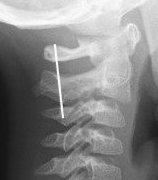

1. Swischuk's Line

- drawn along spinolaminar line C1 & C3

- C2 should be within 1.5 - 2mm of this line

2. Pseudosubluxation will reduce with extension